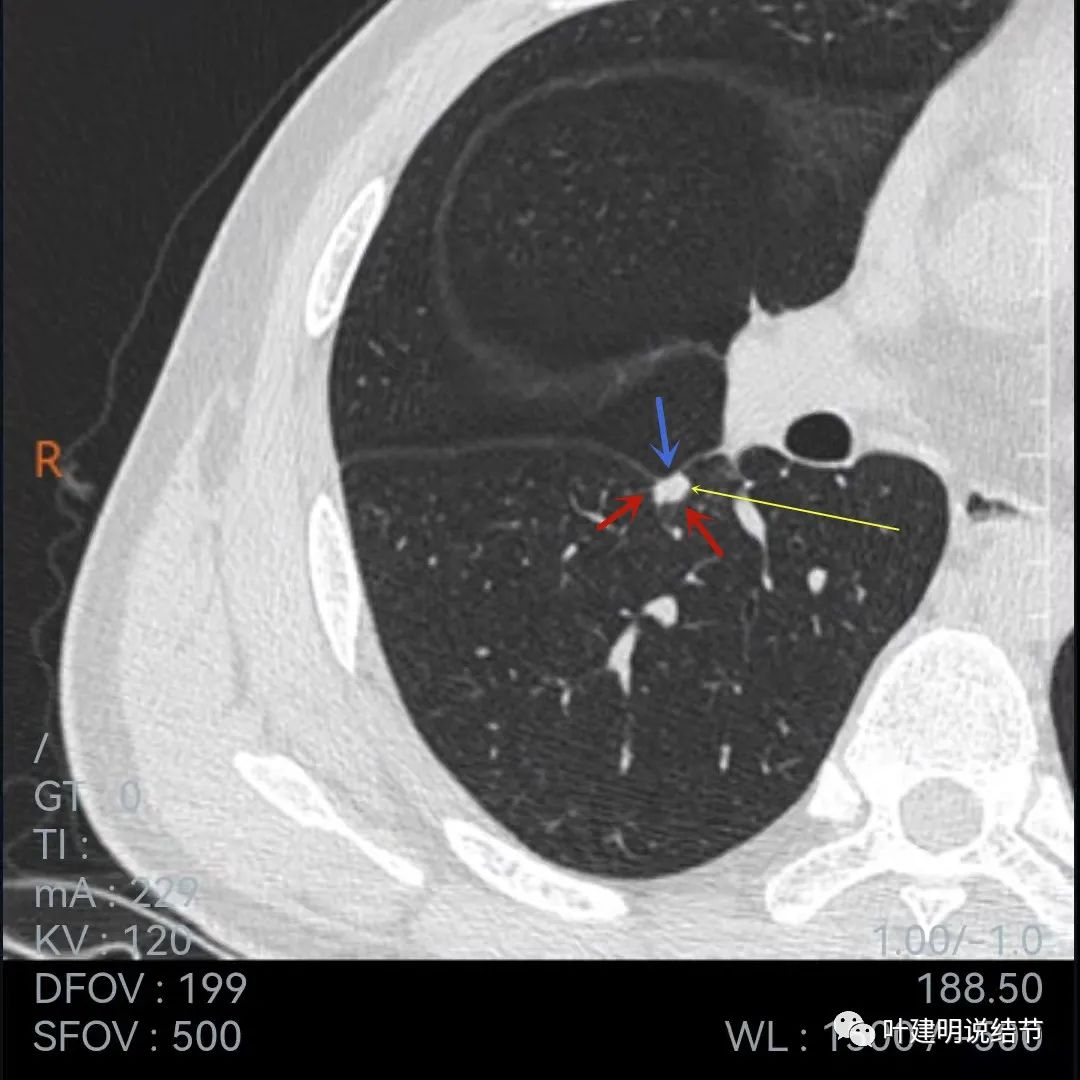

再来看下面薄一点的,也是2020年7月的图像:

叶间胸膜牵拉

牵拉明显

中间密度略低(黄色箭头),前部边缘似有少许毛刺或毛糙的感觉(紫色箭头)

叶间胸膜牵拉凹陷

上图层面密度略不均

与前一年相比,病灶略有不同,感觉边缘粗糙起来,胸膜凹陷较前明显,但因为薄层与非薄层的区别,可比性略差。